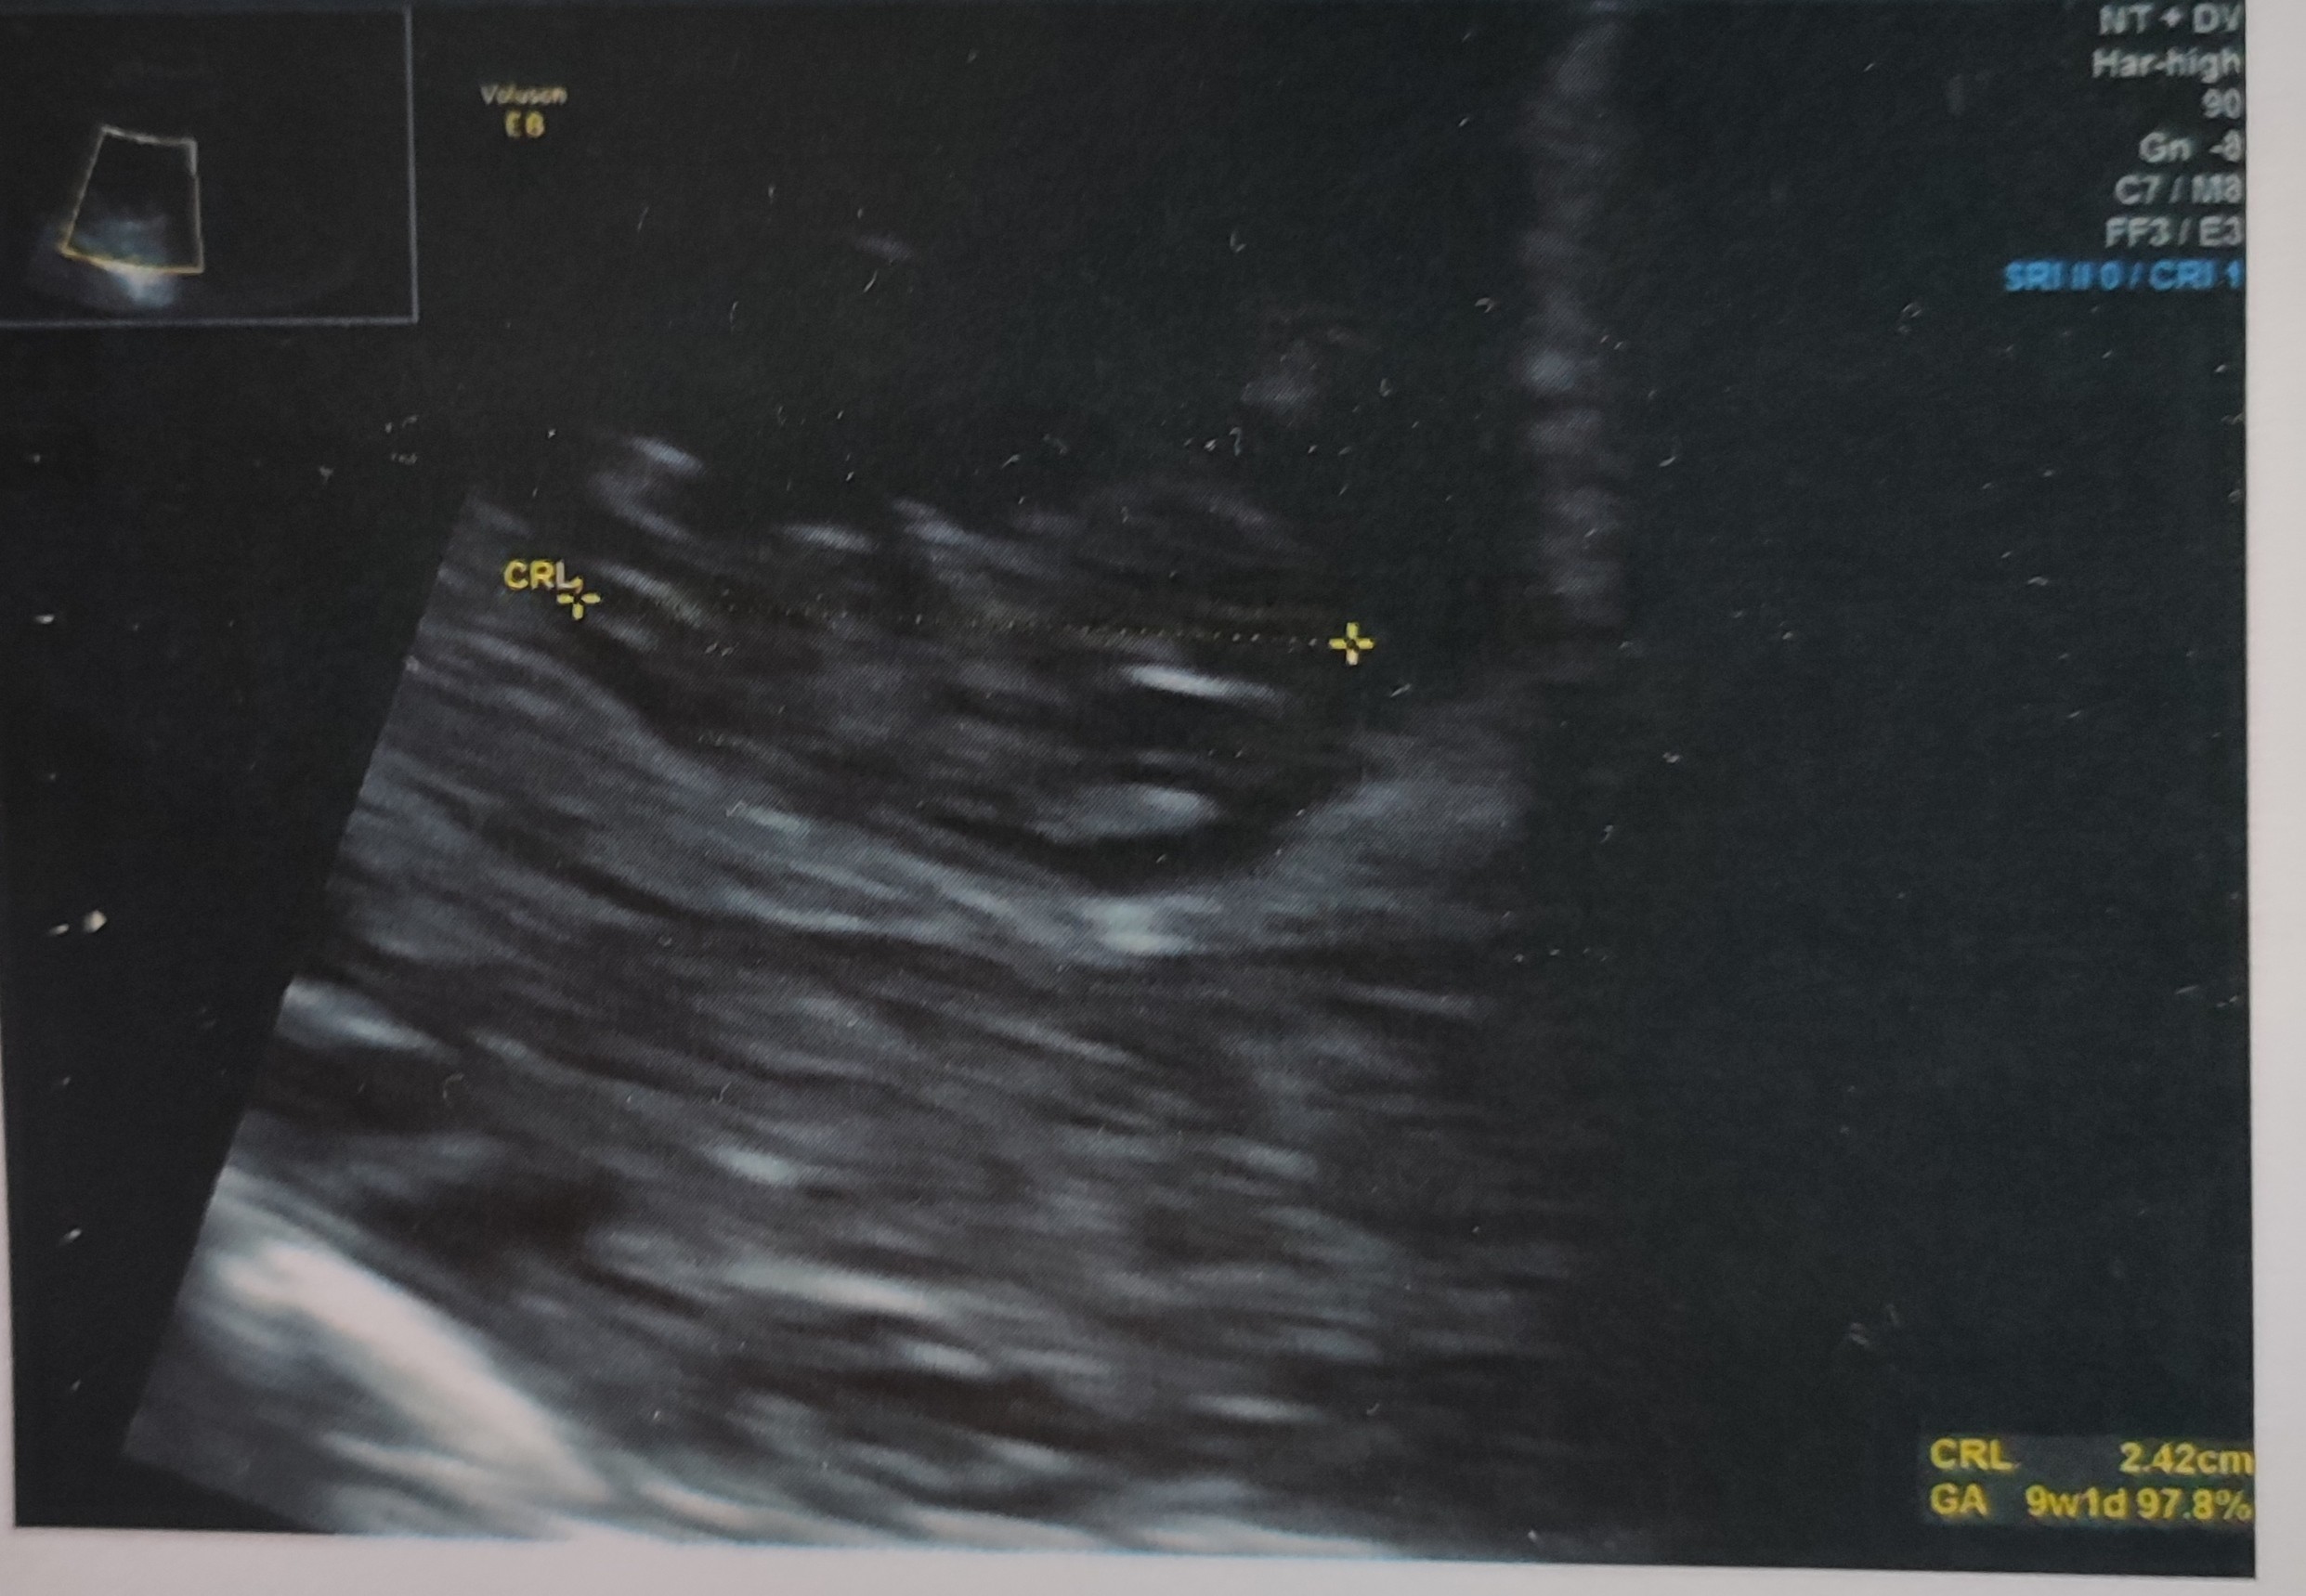

To moja pierwsza ciąża ,mam 37 lat i właśnie zaczynam 9 tydzień (według USG ,z daty miesiączki ciąża tydzień młodsza ).W oczekiwaniu na pierwszą wizytę na NFZ poszłam jeszcze wcześniej na wizytę prywatną na której lekarz potwierdził ciążę i zrobił USG i mogłam zobaczyć bijące serduszko .Po kilku dniach od wizyty prywatnej doczekałam się tej na NFZ gdzie lekarz również potwierdził ciążę natomiast powiedział że serduszka jeszcze nie widać ???? Stres miałam wtedy niesamowity ale to chyba rzeczywiście kwestia sprzętu jakim dysponuje gabinet. Wczoraj miałam się zgłosić na badanie krwi papaa jednak położna w rejestracji zasugerowała ,że to chyba jednak za wcześnie ....poprosiła lekarza o konsultację a ten zaprosił mnie do gabinetu i mówiąc ,że jeszcze zobaczy maluszka .Zrobił mi pierwsze USG przez brzuszek i potwierdził 9 tydzień (fasolka ma prawie 2.5 cm ) serduszko pięknie widoczne więc taka miałam jeszcze niespodziewana wizytę z którą w dodatku nie pobrano opłaty .Dziś mam wizytę w gabinecie NFZ więc zapewne będę miała kolejne USG na którym doktor wreszcie zobaczy serducho 😀 .W zasadzie to chyba moja ostatnia wizyta na NFZ ,zależy mi tylko na przedłużeniu L4 gdyż czuje się fatalnie a jeszcze dopadła mnie infekcja gardła .Mam nadzieję ,że uzyskam L4 bo na pierwszej wizycie doktor powiedział że "ZUS bierze mu się za dupę" i mam sobie nie myśleć ,że całą ciążę przesiedze na L4. Na ta chwile faktyczne czuje się słabo więc mam nadzieję , że się zlituje i jeszcze mi wypisze żebym mogła doczekać do wizyty prywatnej która mam 15 grudnia.Sama pracuje w gabinecie stomatologicznym i szczerze mówiąc nie mam ochoty wdychać cudzych zarazków i ryzykować choroby .Ponadto każdego dnia wykonujemy mnóstwo zdjęć RTG a przebywanie w pomieszczeniu obok choć niby jest bezpieczne to w tym okresie wolałabym tego uniknąć i poprostu chronić nas .Pozdrawiam wszystkie mamcie i trzymam za nas kciuki 😀

• IMG_20221207_112822.jpg

IMG_20221207_112822.jpg

585,1 KB · Wyświetleń: 80